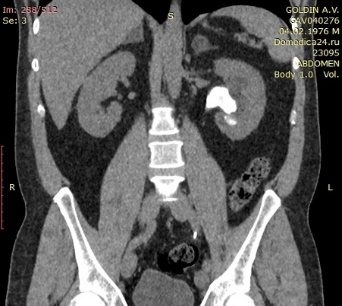

Компьютерная томография живота, таза (рис. 4, рис. 5).

Краткая информация о пациенте Пациент Г., 45 лет. Считает себя больным в течение года, когда впервые был госпитализирован в городскую районную больницу с левосторонней почечной коликой. На момент обращения выявлен камень левого мочеточника, по поводу чего (10.08.2020 г.) выполнялась контактная уретеролитотрипсия слева, установка внутреннего мочеточникового стента. В последующем для удаления стента в стационар не обращался. С июня 2021 г., стал отмечать боль в поясничной области слева. Обследовался амбулаторно, по результатам компьютерной томографии диагностированы внутренний мочеточниковый стент слева, камень в мочевом пузыре на дистальном конце стента, размерами до 3,8 см и коралловидный камень в левой почке, размерами до 3,4 см. Госпитализирован в клинику урологии для оперативного лечения.